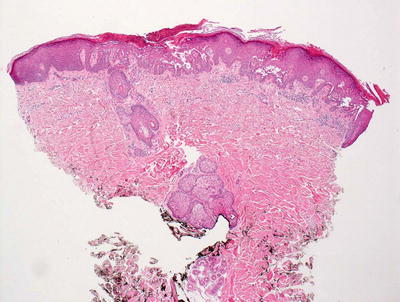

3.11.2 Histology

The blistering in epidermolysis bullosa simplex occurs within basal keratinocytes. This separation is within the cytoplasm, beneath the nuclei. Thus, the histologic appearance is that of a blister that is above the basement membrane zone, located within the basal layer of the epidermis (Fig. 3.27). In many cases, however, it is difficult to detect the small residual fragments of basal keratinocytes that remain attached to the floor of the blister, giving rise to the appearance of a subepidermal blistering process. The small fragments of basal keratinocytes tend to retract and lie flat along the basement membrane and may not be easily detected on H&E stains [92]. Ultrastructural analysis will easily resolve the level of the blistering (Fig. 3.28) [93]. Since this is a mechanically induced blistering disorder, an inflammatory infiltrate is not ordinarily part of the process, except as a secondary phenomenon that is seen in older lesions. Histologic scarring is not seen in epidermolysis bullosa simplex.

Fig. 3.27

Epidermolysis bullosa simplex has an intraepidermal split within the lower half of basal keratinocytes (photo courtesy of Dr. John Hicks, Texas Children’s Hospital, Houston, TX)

Fig. 3.28

A blister is seen above the basement membrane zone with arrows indicating keratinocyte cytoplasm at the base of the blister cavity in epidermolysis bullosa simplex (photo courtesy of Dr. John Hicks, Texas Children’s Hospital, Houston, TX)